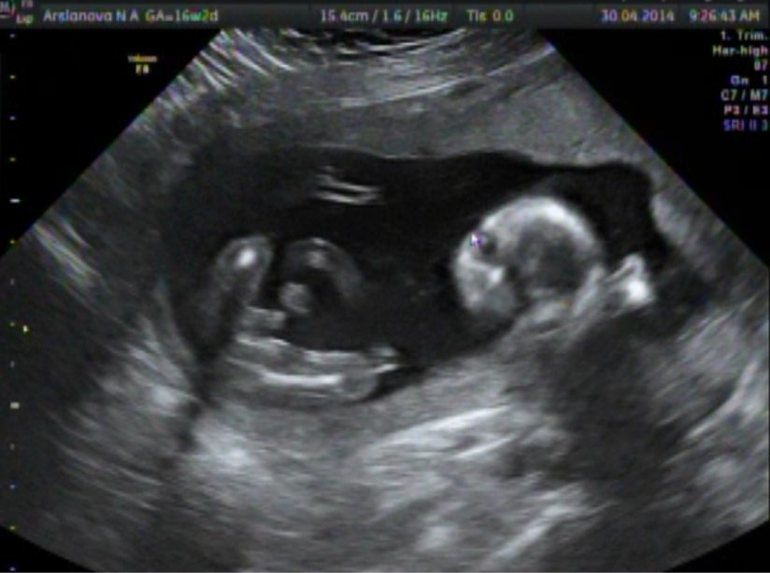

Записалась на УЗИ аж в 9 утра - ненормальная, итак не высыпаюсь.

На УЗИ я возлагаю большие надежды ) Прежде всего узнать пол человека - для мальчика у меня уже есть имя.

А кроме того, уже 17 неделя, а я этого тихушника совсем не чувствую. В совокупности с отсутствием живота, даже не верится что я беременна.